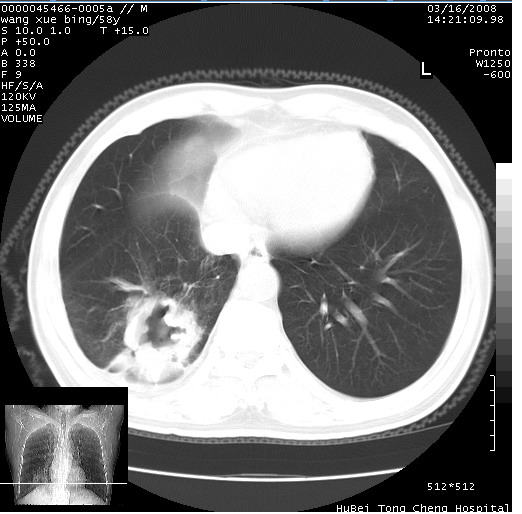

患者 男,58岁。咳嗽、咯血3月余。

胸部cr x线片提示:1)右下肺脓肿。2)右下肺周围型肺癌不排除。建议:行ct扫描检查。

胸部ct轴位平扫(层厚10mm,螺距1.5,重建间隔10mm),图像如下:

右肺下叶团块及不规则空洞,内壁不规则,外缘见粗长毛刺,临近胸膜明显增厚并与病灶关系密切。支持考虑:右肺肺脓肿!建议穿刺病理检查待除外周围型肺癌!

右肺下叶见不规则厚壁空洞,内壁不规则,外缘见粗长毛刺,临近胸膜明显增厚并与病灶关系密切。支持考虑:周围型肺癌!

右肺下叶周围型肺癌伴空洞形成!征象比较明显!分叶、毛刺、胸膜凹陷征、厚壁空洞,壁结节!

空洞壁厚,不规则,其内可见壁结节,周围可见毛刺及阻塞性炎变,多考虑癌性病变.

空洞内壁不规整,有壁结节,周围有毛刺,支持癌性空洞。